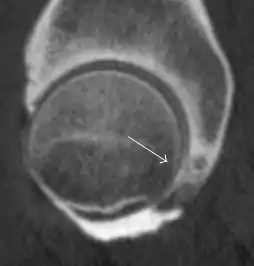

Synovial chondromatosis can be confidently diagnosed by X-ray when calcified cartilaginous chondromas are seen. However, other synovial proliferative processes, such as pigmented villonodular synovitis, require MRI for accurate diagnosis, although noncalcified synovitis can be suspected in radiographs by indirect signs, such as soft tissue swelling and/or erosions in the femoral head, femoral neck, or acetabulum (Figure 7).[1]

Figure 7:

Axial CT image of pigmented villonodular synovitis eroding the posterior cortex of the femoral neck.[1]

X-ray of synovial chondromatosis.[1]

CT of synovial chondromatosis.[1]

In synovial proliferative disorders, MRI demonstrates synovial hypertrophy. In the case of PVNS, characteristic foci of low signal intensity related to hemosiderin deposition are better seen on gradient echo T2* images (Figure 7). In the case of synovial osteochondromatosis, the synovial hypertrophy is accompanied by intermediate signal cartilaginous loose bodies and/or low signal calcified loose bodies.[1]